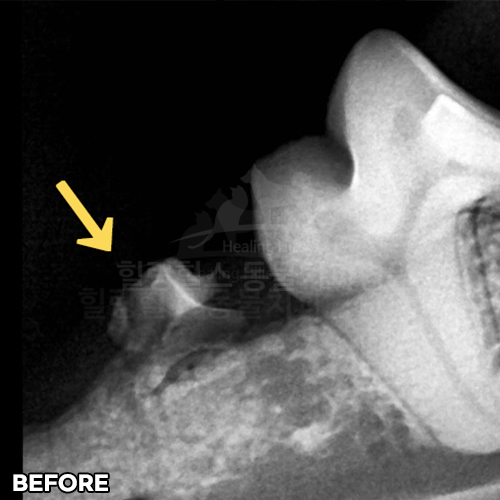

• [강아지 매복치 발치]

샘플